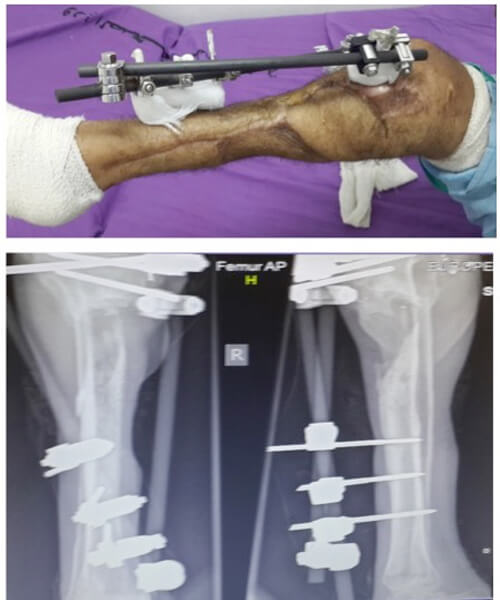

Three months from this salvage there were no signs of osteomyelitis yet (Figure 12). There was no motor or sensory neural recovery. Regular follow-up and monitoring continue. The surgery has afforded the patient time to consider his options whilst the full debridement prevented imminent sepsis. If the boy elects to keep this limb, the function will always be poor and not consistent with the mobility a 17-year-old should enjoy whatever reconstructive options are applied. Amputation, good rehabilitation and a good prosthesis would give him superior mobility.

Figure 12: Appearance of leg three months from salvage surgery and bone shortening.

Compete debridement was undertaken to eradicate septic foci. Once clean, a Masquelet type procedure and closure with the medial adhoc perforator flap was undertaken providing limb salvage (Figure 16).

Figure 16: Flap cover following thorough bone debridement and Maquelet cement plug.

Split skin graft covers the flap donor site and any remaining soft tissue defects.

The patient was discharged home 10 days later with no new signs of infection and all areas closed by flap and SSG. At three months review, he was mobile on one leg with crutches. He was well and grateful to have the time to consider his options; he could accept the functional limitations of the leg. He was considering elective amputation if he could be guaranteed a good prosthesis. One year from surgery (Figure 17), he still retains the functionless leg with no episodes of clinical osteomyelitis but minimal chances of bone union. He will have to come to his decision shortly.

Figure 17: one year post surgery.